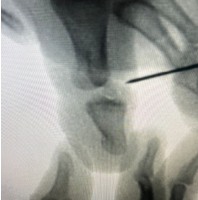

Informed consent was obtained from all participants. Demographic details and relevant medical history were collected using a structured proforma. Clinical examination and surgical intervention were carried out using standard procedures at the SBMCH. [Fig. 1] [Fig. 2] [Fig. 3] Postoperative evaluation for implant loosening was done through serial radiographs, specifically assessing for radiolucency at the bone-cement interface. Functional outcomes were assessed 26 using the CONSTANT-Murley score and UCLA shoulder score. All data were entered in Microsoft Word and analyzed using SPSS software version 24. [Fig. 4].

Figure 3: Inter-operation image.